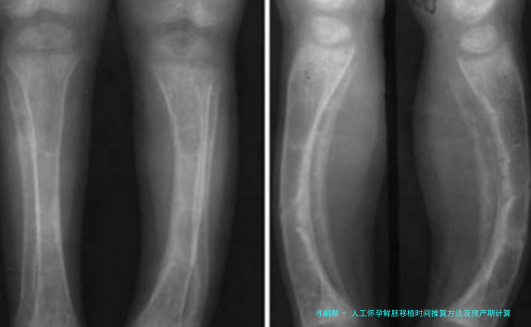

五、B超动态修正机制

孕早期通过量测胚芽长度(CRL)邃密调节孕周:

| 胚芽长度(mm) | 对应孕周 | 允许误差范围 |

|---|---|---|

| 3-5 | 6周+3天 | ±3天 |

| 16-18 | 8周+2天 | ±2天 |

胎心出现时间窗为孕5-6周,晚在自然中妊娠周期一周属正常范围。